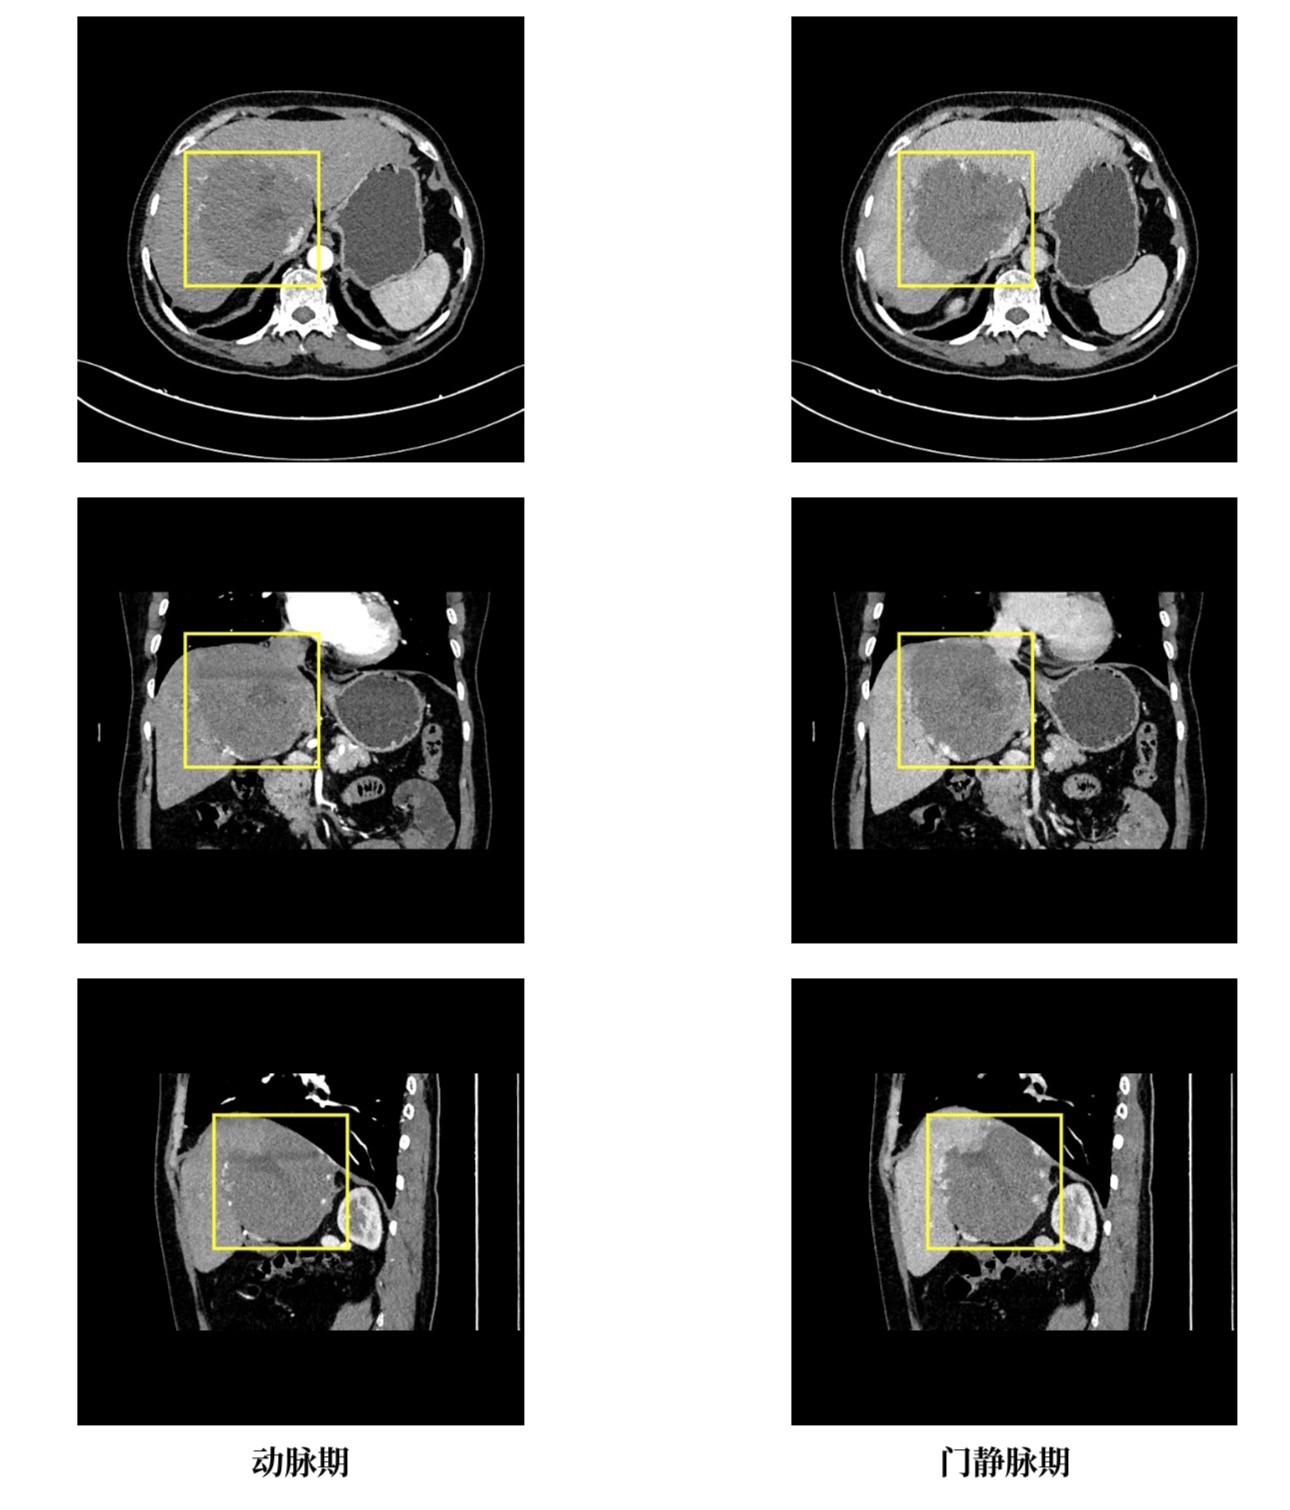

医生介绍,来自毕节市的张女士,经检查发现肝右叶-左内叶及尾状叶存在巨大海绵状血管瘤,此病变累及肝右叶-左内叶及尾状叶区域,毗邻肝脏重要血管,对周围胆管已形成压迫侵犯,解剖关系错综复杂,手术中稍有不慎便可能引发大出血、血管损伤等致命风险。因该手术因病变位置刁钻、解剖结构复杂,被业内视为肝脏外科微创领域的“硬骨头”。面对这一棘手情况,省医肝胆外科二部迅速组建多学科诊疗小组,反复研讨患者的影像学资料与身体指标,精准规划手术路径,最终敲定腹腔镜微创治疗方案。